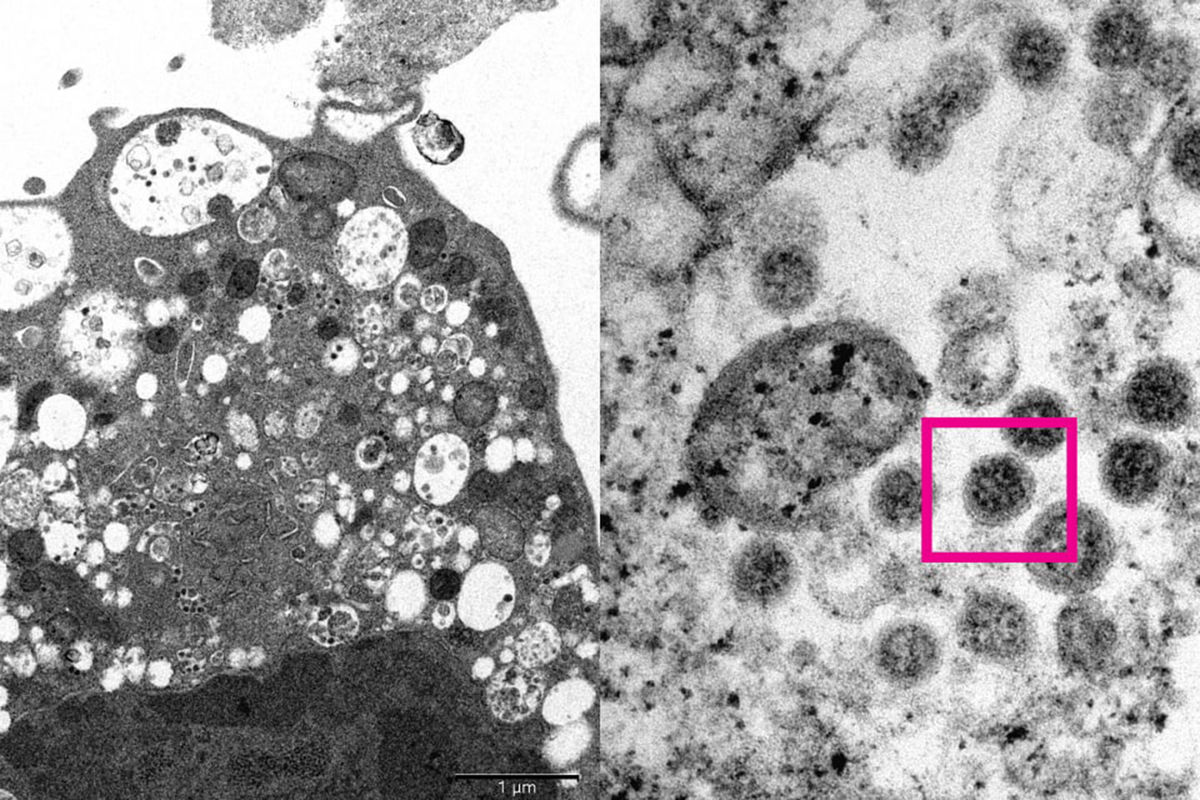

Опубликована электронная микрофотография «омикрона»

Университет Гонконга опубликовал фотографию нового штамма коронавируса «омикрон», снятую с помощью электронного микроскопа. Об этом сообщает РИА «Новости» со ссылкой на заявление университета.

На снимке запечатлена зараженная «омикроном» почка обезьяны, рассказали в университете. Изображение распространяется с малым и большим увеличением.

По словам авторов, на неувеличенном изображении видны поврежденные клетки с набухшими везикулами, в которых содержится вирус — маленькие черные частицы, на подробном — шарообразные вирусы с шипами, напоминающими зубцы короны.